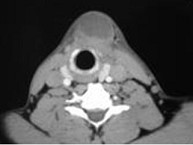

| 八岁患者,男性,因颈前正中包块6年入院,查体:颈前正中舌骨下方可触及一圆形包块,囊性,无压痛,随吞咽上下活动。 |

8.患者肿块图像及影像学检查结果见下图,本患者应考虑为 ( )![]() ![]() ![]() ![]() |

| 正确答案:8.A;9.A |